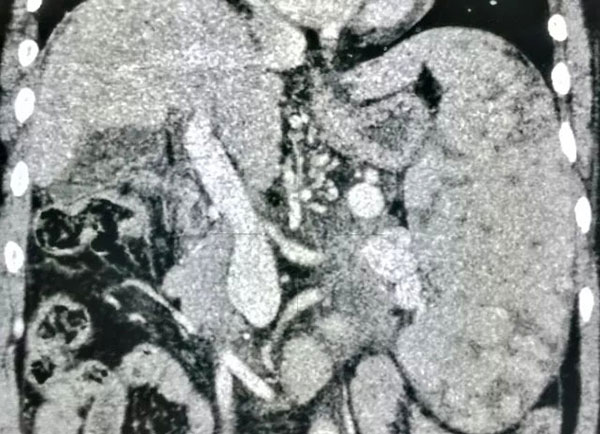

CT发现王阿姨脾脏非常大,已经远远大于肝脏体积,已经成为巨脾了。为了方便理解,小编将王阿姨的脾脏和正常的脾脏作一对比。

图二红线围绕的是王阿姨的脾脏,图三红线围绕是正常人的脾脏。以肝脏大小作为比较,王阿姨脾脏远远大于她的肝脏,而正常脾脏大小像图二一样,远远小于自身肝脏体积。

术后三个月,六个月,一年复查,能看出脾脏体积逐渐明显缩小吗?脾脏周围点状的黑色部分就是坏死的皮质。